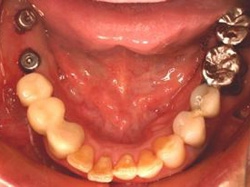

両側5歯症例

両側5歯症例両側5歯症例両側5歯症例 主訴-義歯のバネが壊れて手前の歯が痛んできた。 術前(旧義歯装着、鏡像) 術前(下顎粘膜面、鏡像)術前(下顎粘膜面、鏡像)術前(下顎粘膜面、鏡像) 術前レントゲン術前レントゲン術前レントゲン 術前口腔内(正面観)術前口腔内(正面観)術前口腔内(正面観)

術後(鏡像)術後(鏡像)術後(鏡像) 術後口腔内(正面観)術後口腔内(正面観)術後口腔内(正面観)もう入れ歯は要らなくなりました。 術後レントゲン術後レントゲン術後レントゲン